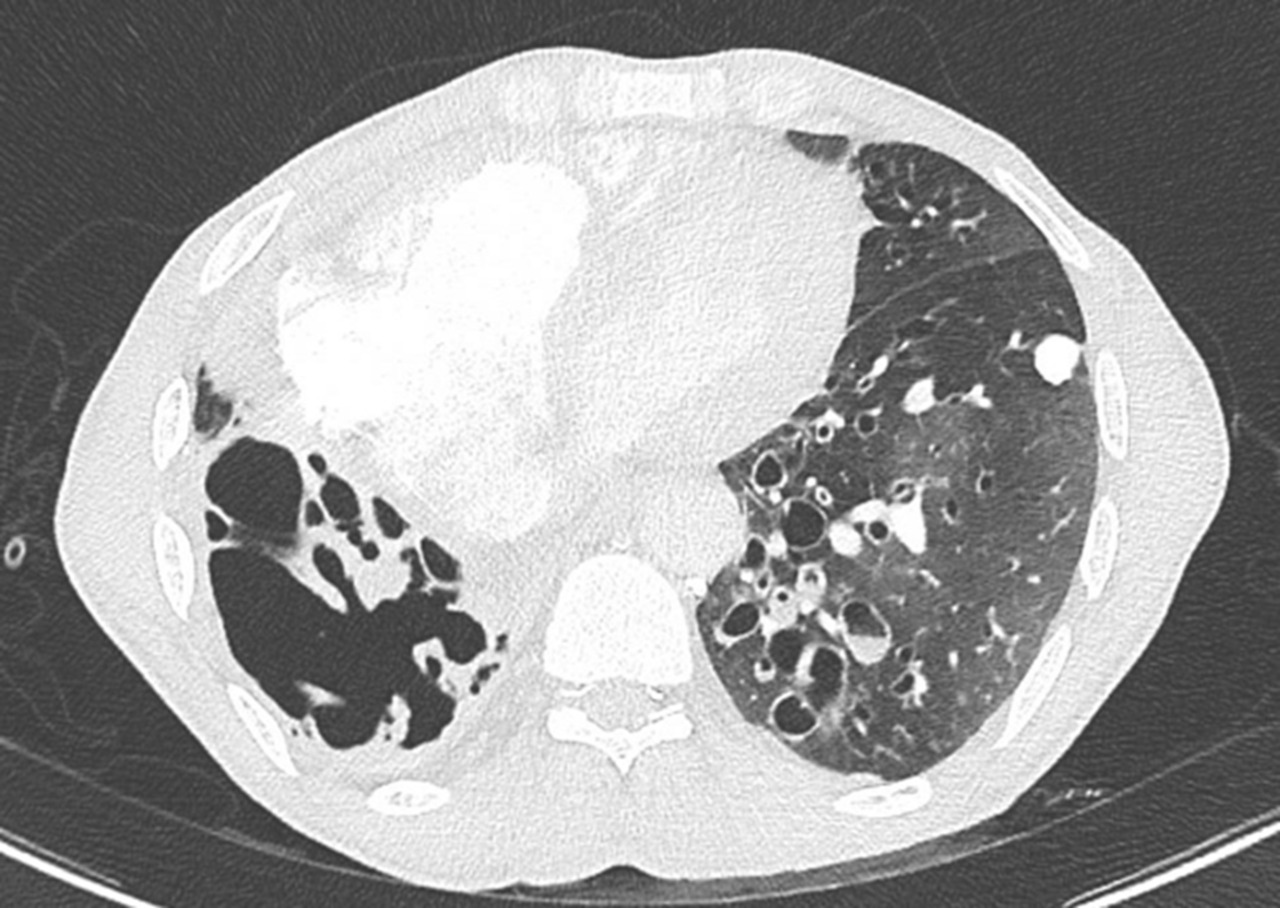

Vous êtes interne de garde aux urgences. Un patient de 71 ans est adressé par son médecin traitant pour dyspnée aiguë.

À l’arrivée, les constantes du patient sont : pression artérielle (PA) = 167/119 mmHg ; fréquence cardiaque (FC) = 114/min ; température (T) = 37,2 °C ; saturation en oxygène (SpO2) = 82 % en air ambiant ; fréquence respiratoire (FR) 30/min.

Présence fréquente d’épanchement pleural en cas d’insuffisance cardiaque mais généralement indolore.